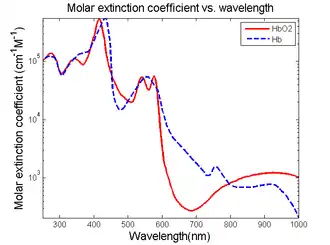

Visible light absorbers (λ = 400 to 700 nm) include oxyhemoglobin, deoxyhemoglobin, melanin, and cytochrome c. Visible light photoacoustic microscopy is particularly useful in determining hemoglobin concentration and oxygen saturation due to the difference in absorption profiles of oxyhemoglobin and deoxyhemoglobin. Real-time analysis can then be used to determine blood flow speed and oxygen metabolism rate.[3] In addition, photoacoustic microscopy is capable of early melanoma detection due to the high concentration of melanin found in skin cancer cells.

Near-Infrared absorbers (λ = 700 to 1400 nm) include water, lipids, and glucose. Photoacoustic determination of blood glucose levels can be used for treating diabetes, while studying lipid concentrations within blood vessels is important for monitoring the progression of atherosclerosis.[2] It is still feasible to quantify and compare deoxyhemoglobin and hemoglobin concentrations at this wavelength, trading deeper tissue penetration for lower absorption.[6]